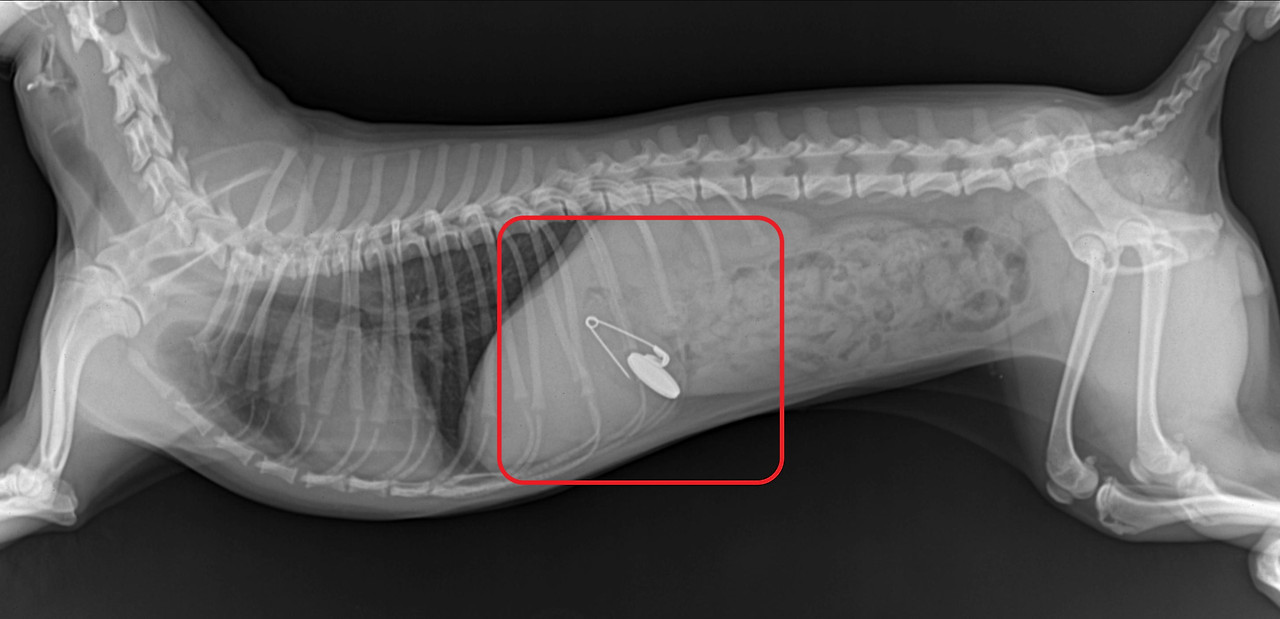

3.jpg

<좌> 식도에 간식이 걸린 경우 <우> 위에 옷핀과 동전이 있는 경우

사진출처 : 24시 센트럴 동물 메디컬센터

"이물을 삼킨 경우에는 어떻게 되나요?"

반려견이 이물을 삼킨 경우에는 반려견의 종류에 따라 다양한 문제를 야기할 수 있습니다.

동전은 구리 중독, 날카로운 플라스틱이나 바늘 등은 위장 천공을 유발하게 됩니다.

덩어리가 있는 이물이라면 소장 폐색으로 응급 수술을 해야 하고

위 내 여러 이물이 정체되어 있으면 만성 위장관 염증을 일으켜서 구토를 하게 됩니다.

이물을 삼킨 경우에는 즉시 병원을 방문해야 하고 평소 집 근처의 24시 동물병원을 알아두는 것이 좋습니다.